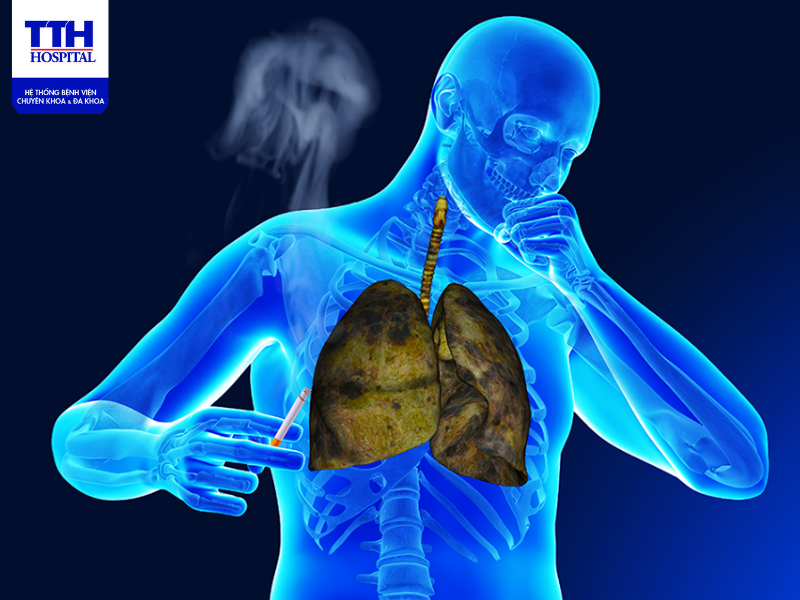

Bệnh lao phổi (tiếng Anh là Pulmonary Tuberculosis) là bệnh truyền nhiễm qua đường hô hấp, xảy ra khi vi khuẩn M.Tuberculosis tấn công chủ yếu vào phổi. Bệnh ho lao phổi dễ gây ra nhiều biến chứng nguy hiểm tới sức khỏe và tính mạng của bệnh nhân.

Vi khuẩn Mycobacterium Tuberculosis là một vi khuẩn ái khí vì vậy vi khuẩn ưa cư trú trong môi trường có nhiều oxy, vì đặc tính này mà vi khuẩn lao thường khu trú ở phổi và số lượng vi khuẩn có nhiều nhất trong các hang lao có phế quản thông.

Bệnh ho lao là bệnh lây lan qua không khí, mầm bệnh không tồn tại trong tự nhiên và không có vật trung gian truyền bệnh. Nguồn lây bệnh chủ yếu là người hoặc động vật mắc vi khuẩn lao, bệnh dễ lây truyền khi người hoặc động vật nhiễm bệnh ho, hắt hơi tạo ra những hạt nước bọt rất nhỏ chứa nhiều vi khuẩn lao lơ lửng trong không khí. Người ta có thể hít những hạt này vào phổi và mắc bệnh.